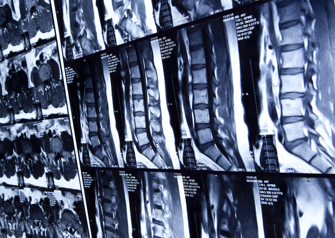

Dr. Frank Phillips, a minimally invasive spine surgeon, was an author of a paper that recently won an NASS Best Paper award.

In todays healthcare environment, there is increasing scrutiny placed on assessing the value of non-surgical and surgical care in the treatment of low back disorders. The study aimed to evaluate the costs of conservative treatment for low back condition in the 6 months prior to spinal fusion surgery.

Conservative treatment in the 6 months prior to lumbar fusion surgery was extremely costly (over $30 million in 8,000 Medicare Advantage patients) related to use of medications, injections, physical therapy and imaging studies. High expenditures on non-surgical care in certain patients with surgical indications, did not avoid the need for lumbar fusion surgery.